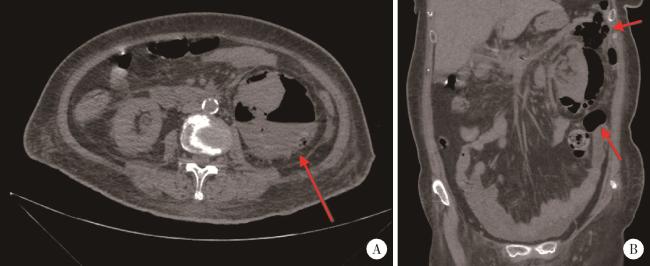

回顾性分析自2016年1月至2025年1月于首都医科大学附属北京积水潭医院泌尿外科诊治的气肿性肾盂肾炎患者,收集患者的基本资料、现病史、既往史、体格检查、相关的辅助检查等,并记录患者的治疗方案及结局转归。根据患者腹部CT结果,采用目前文献报道应用最广泛的Huang等[5]学者提出的分级标准,将所有EPN患者分为4级,Ⅰ级:肾实质内出现气体,肾周无积气;Ⅱ级:肾内及肾周均有气体,但局限于肾脂肪囊内,未超出Gerota筋膜;ⅢA级:气体超出Gerota筋膜,蔓延至肾旁间隙,但没有腹膜后广泛积气或积脓;ⅢB级:除了肾旁间隙受累外,还伴有腹膜后广泛积气或积脓;Ⅳ级:双侧肾脏受累或孤立肾受累,同时伴有败血症等全身严重感染表现。图 1为1例典型的ⅢB级EPN患者CT平扫表现。

图1 1例左肾EPN患者的CT平扫结果,分级ⅢB级

Figure 1 Non-contrast CT images of a patient with left renal EPN, classified as grade ⅢB

A, axial CT image demonstrated extensive perirenal gas and fluid accumulation with an air-fluid level (red arrow); B, coronal CT image revealed signi-ficant retroperitoneal gas (red arrow). EPN, emphysematous pyelonephritis.